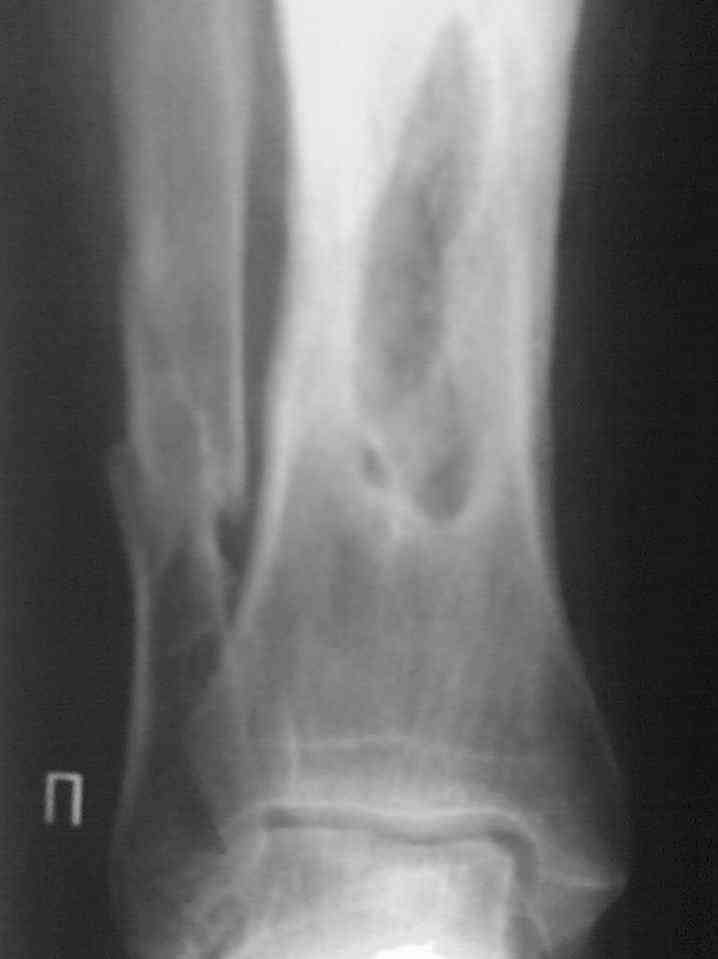

Выкладываю снимки в хронологическом порядке. Снмки все какие есть у больного.